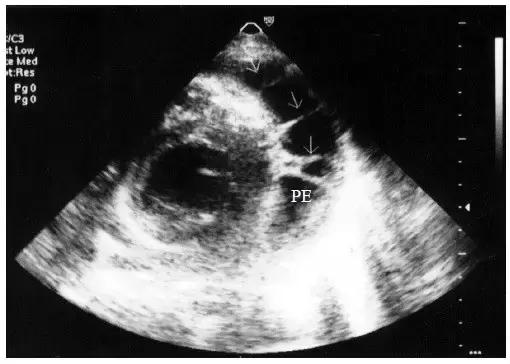

【少量心包积液】

液体仅潴留在左心室后壁和侧壁心包腔内,内径<10mm(图1)。

图1 少量心包积液的二维超声心动图表现

左心室后壁心包腔内少量液性暗区,内径< 10mm